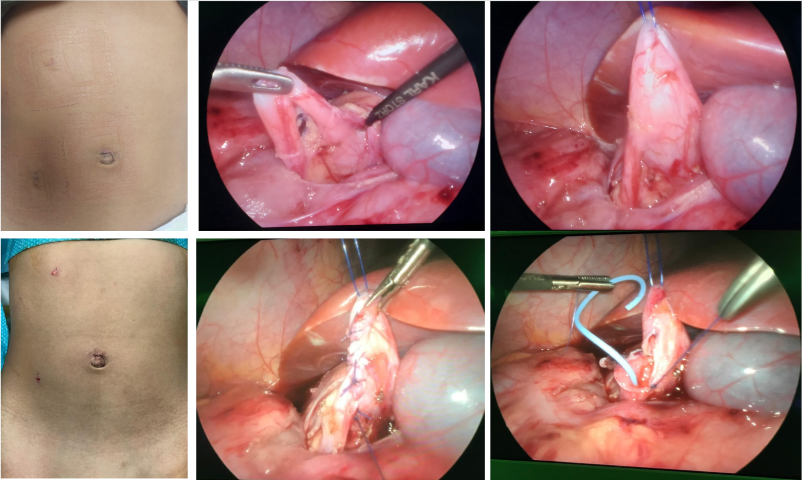

A 4 years old child with bilateral grade 4 Vesico-ureteric reflux and reflux nephropathy had Pneumo-Vesicoscopic ureteric reimplantation. Child had a very comfortable post operative period and discharged on 3rd post op day. This procedure is a paradigm shift from the conventional open cross trigonal ureteric reimplantation where a Pfannensteil (lower transverse) incision is usually made , bladder is opened and post surgery ureteric catheters are exteriorized per abdomen, requiring 7-10 days of postop recovery ,significant amount of analgesia, leaving a large scar; or conventional Laparoscopic extra vesical reimplantation ( not always suitable for dilated high grade refluxing ureters). In this procedure all the reimplantaion steps were carried out entirely within the domain of Urinary bladder by 3mm minilaparoscopic instruments , without any post op stents. The child had very comfortable recovery with minimal analgesia and left with barely appreciable scar.

This relatively new technique has tremendously improved the quality of life of the reimplantation kids